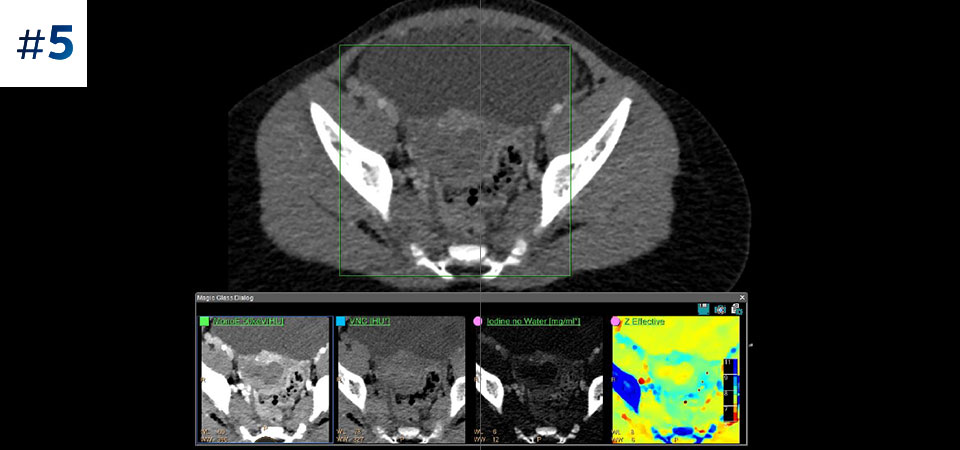

Prend en charge toutes les catégories de patients Du patient pédiatrique au patient bariatrique.

Observez la différence entre le scanner à détection spectrale et le scanner classique

Découvrez les avantages du scanner à détection spectrale